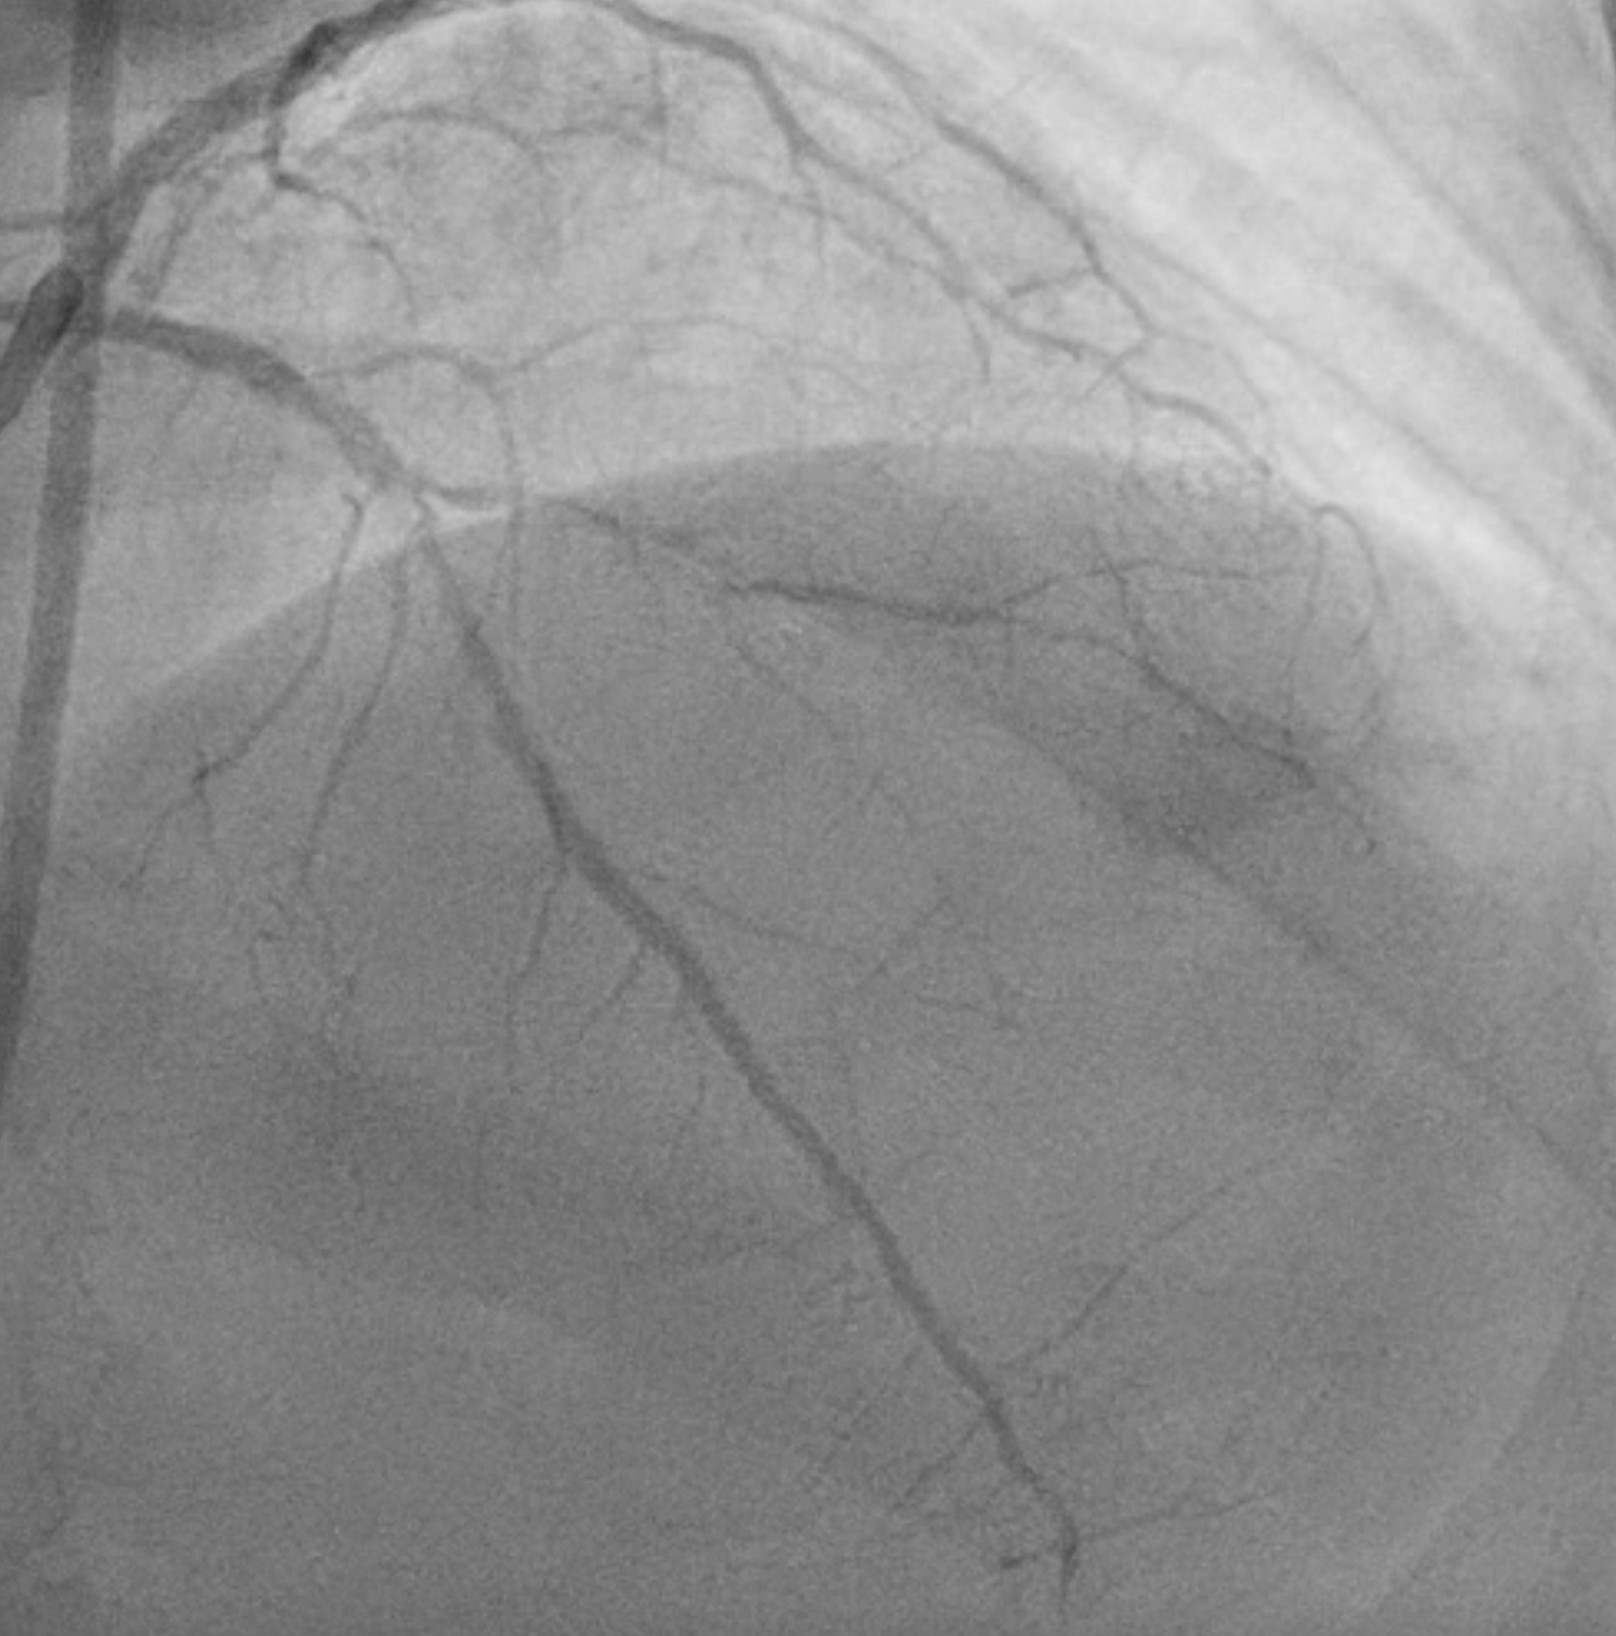

PCIof the LAD was performed via femoral access using a BL 3.5/7F guiding catheter.A Runthrough Hypercoat wire was advanced distally without difficulty. The OCTcatheter failed to cross the lesion, and a 2.5 ¡¿ 15 mm scoring balloon couldnot pass the mid LAD. A microcatheter was inserted, and the wire was exchangedfor a Rotawire. Rotational atherectomy was performed using a 1.25 mm burr withshort, gentle pecking runs at 180,000 rpm, followed by upsizing to a 1.5 mmburr for three runs at 200,000 (2 times) and 160,000 rpm. The burr advancedsmoothly with improved tactile feedback, suggesting successful plaquemodification. The wire was exchanged back to a Runthrough, and OCT (DragonflyOPTIS) imaging showed an MLA of 1.43 mm©÷ at mid LAD with severe 360¡Æ calcification(0.9 mm thick, 41 mm long) and a napkin-ring pattern. A 2.5 ¡¿ 15 mm cuttingballoon was used with multiple 14–18 atm inflations, producing a visible¡°crack¡± in the calcified cap. Angiography and repeat OCT confirmed the calciumfracture. A 3.0 ¡¿ 46 mm DES was deployed from the ostial to distal LAD at 14atm and post-dilated with a 3.5 mm NC balloon proximally. Final angiographyshowed TIMI 3 flow. OCT demonstrated excellent stent expansion (MSA 7.78 mm©÷proximal, 3.28 mm©÷ distal) without dissection and with 107% stent expansion.

This case shows the Rota-Cut strategy transforms a high-risk, unpredictable intervention into a controlled and successful one on a severely calcified "napkin ring" coronary lesion that is resistant to standard balloon dilation. Rotational atherectomy will reduced the volume of calcific plaque and cutting balloon will cause calcium fracture to facilitate optimal stent expansion and apposition confirmed on intravascular imaging and prevent stent failure in the future.